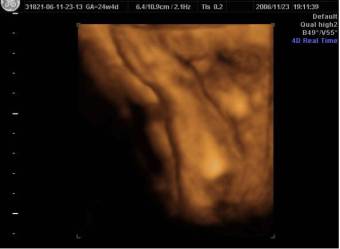

4D-s uh-val már 12 hetesen is láthatják a nemét, ha úgy mutatja magát, de a dokik 16 héttől szeretik mondani. Szerintem a cici már nem kéne, hogy feszüljön, ez az elején jellemző. Nekem is csak max 6 hétig volt ez…viszont már kb 2x akkorák, mint voltak, tök fura…mert amúgy az enyémek tök kicsik :p Megkérdezhetem, hogy te Pesten nőttél fel, vagy máshonnan származol? Ha igen, honnan? Ismerősek nekem ezek a képek…persze lehet csak itt a bneten láttam valahol, mert régebben nézelődtem minden féle topikban.